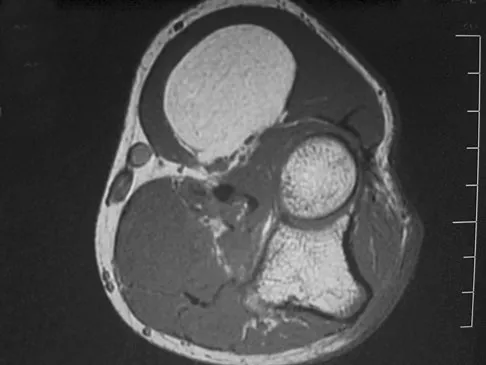

A 35-year-old woman who is a recreational runner reports posterior knee pain and tightness in the knee with flexion during running. She denies any history of trauma. Examination reveals normal patellar glide and tilt and no patellar apprehension. Range of motion is 5 degrees to 120 degrees, and quadriceps function and knee ligamentous examination are normal. Radiographs are normal. An MRI scan is shown in Figure 18. What is the most likely diagnosis?